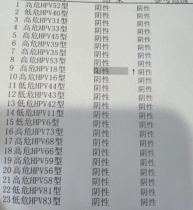

HPV16、18型高危阳性

做为教师的我,查询很多资料后非常清楚的知道HPV意味着什么,它会造成什么样的后果。但我怎么都没有想到HPV感染会让我饱受折磨。生完孩子后,下面总感觉不舒服。恰好到了体检的时候我也查了HPV,结果查出HPV16、18高危阳性。

万万没想到的是,就是这个【抗HPV三联疗法】,前后调理3个周期,彻底帮我摆脱HPV高危病毒感染,拿到全阴的检查结果后,我激动在医院走廊里放声大哭。

亲眼看到全部转阴报告单,我惊讶不已!赶紧再次联系老师,表达感谢的同时,也向【抗HPV三联疗法】老师了解具体的调理步骤,分享给大家!可以加老师微信号17753103098☞查看二维码添加可以免费领取方案, 老师一定会帮大家解决的。

我感染HPV病毒四年多,是16、18、6、52型的,还有宫颈病变。用了四个疗程的抗HPV三联疗法基本改善了。我这还有好转的报告单,大家看一下。